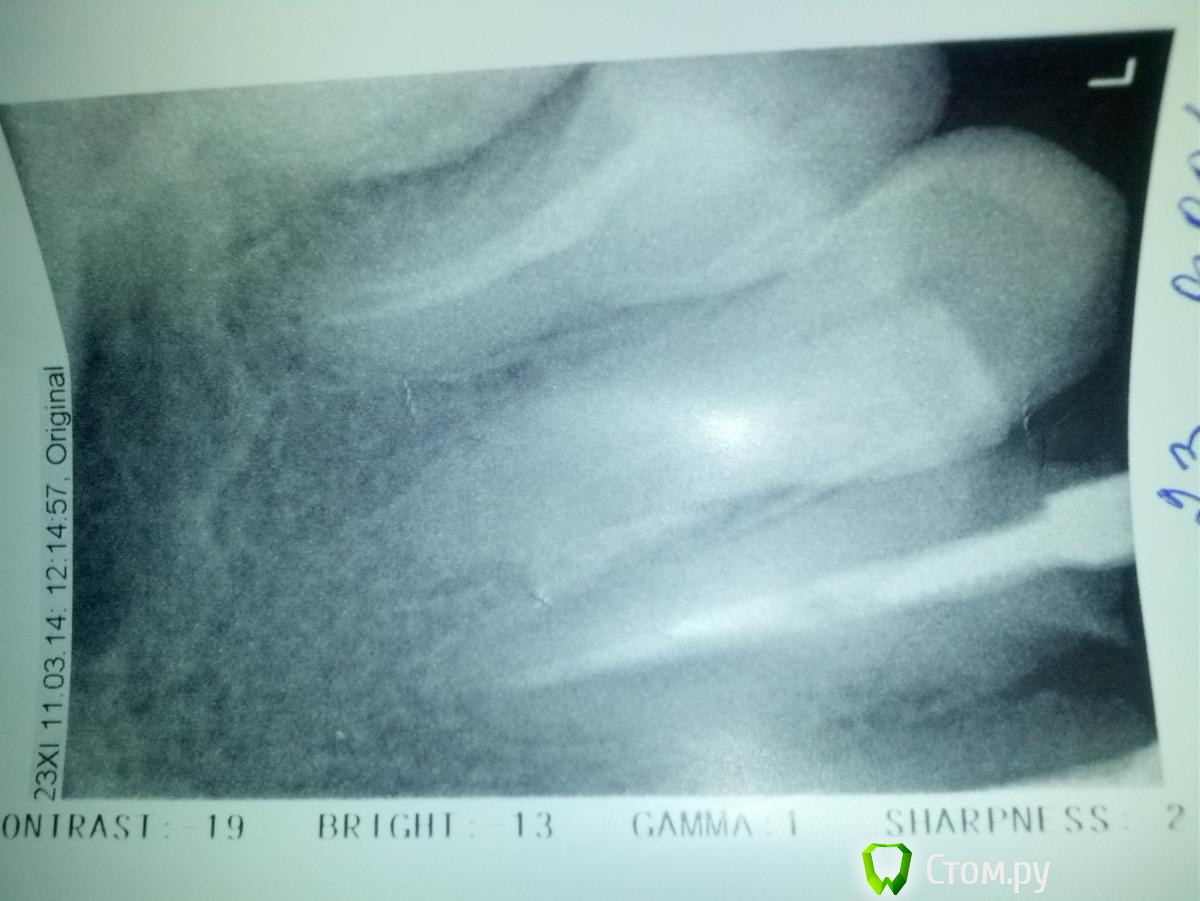

bogu Опубликовано 11 марта, 2014 Поделиться Опубликовано 11 марта, 2014 (изменено) Сняла металлокерамику, которая простояла 11 лет, из-за нарушения эстетики (начала появляться метал.полоска между десной и коронкой), решила поставить цирконий, сняли коронки, врач рекомендовал поменять пломбы и увеличить коронковую часть, т.к. под металлокерамику было сильно обточено. Терапевт говорит, что коронковая чать у зубов разрушена и стекловолокно ставить нет смысла, может обломиться, настаивает на вкладках, врач-ортопед, говорит, что вкладка из диоксида циркония не будет амортизировать и может треснуть, тогда ее уже не достанешь.(хотя судя по всему финансово должен был бы быть заинтересован во вкладках . в зубах стоят штифты металлические, один сегодня достали, пока накрыли врем пломбой-не знаю что делать...Зубы передние резцы и клык (5 ед). До этого 11 лет стоял мост, сейчас хотела поставить отдельные.. Посоветуйте, какие варианты есть... На КТ каналы заполнены, а сегодня на визиографе есть некоторые чуть светлее участки, как терапевт сказала, не пустота, но неравномерно паста лежит..(не знаю, видно ли будет на фото) что делать? оба врача высказали свои мнения, к одному решению не пришли, ответственность за решение переложили на меня(( Клиника где протезируюсь, одна из лучших в городе Изменено 11 марта, 2014 пользователем bogu Ссылка на комментарий

bogu Опубликовано 11 марта, 2014 Автор Поделиться Опубликовано 11 марта, 2014 Выложила Ссылка на комментарий